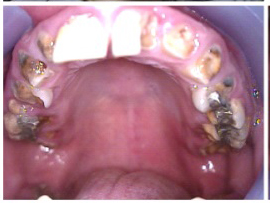

The patient in Figure 10 through Figure 12 was pregnant when she presented for dental treatment. The pregnancy was unplanned and she had had a lack of prenatal care. Continuing meth use during the pregnancy resulted in a positive toxic baby. She stated that she had just stopped using meth and had entered a rehabilitation facility a few days before. She was brought to the author’s clinic with a toothache. Note that as seen in these images, extreme accumulation of plaque, lack of oral hygiene, and severely decayed and missing teeth are classic manifestations in meth users.

Fig 10. Accumulation of soft plaque is typical of oral hygiene neglect associated with the use of methamphetamine.

Figure 10

Fig 11. Note demineralization of smooth surfaces, carious lesions at the gingival margins, and associated inflammation of the periodontium.

Figure 11